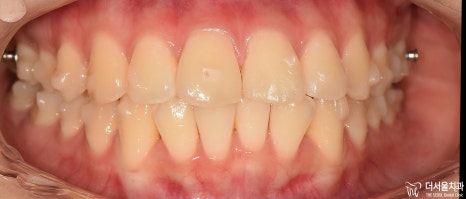

치료 진행, 1차 경과

치아의 표면에 인비절라인의 치아 이동 핵심 원리인 어태치먼트들이 붙여져 있습니다.

뾰족뾰족 튀어나온 것들이, 투명 템플릿과 서로 맞물려서 상호작용을 일으키는거고

이 힘 때문에 앞서 보여드렸은 클린첵 시뮬레이션 결과를 그대로 환자께 드릴 수 있는겁니다.

13개월 이라는 교정 치료기간이 소요되었으며, 앞쪽으로 뻐드러져 있던 앞니들도

incisal angle 변화에 따라서 제 위치를 되찾은 것을 볼 수 있습니다.